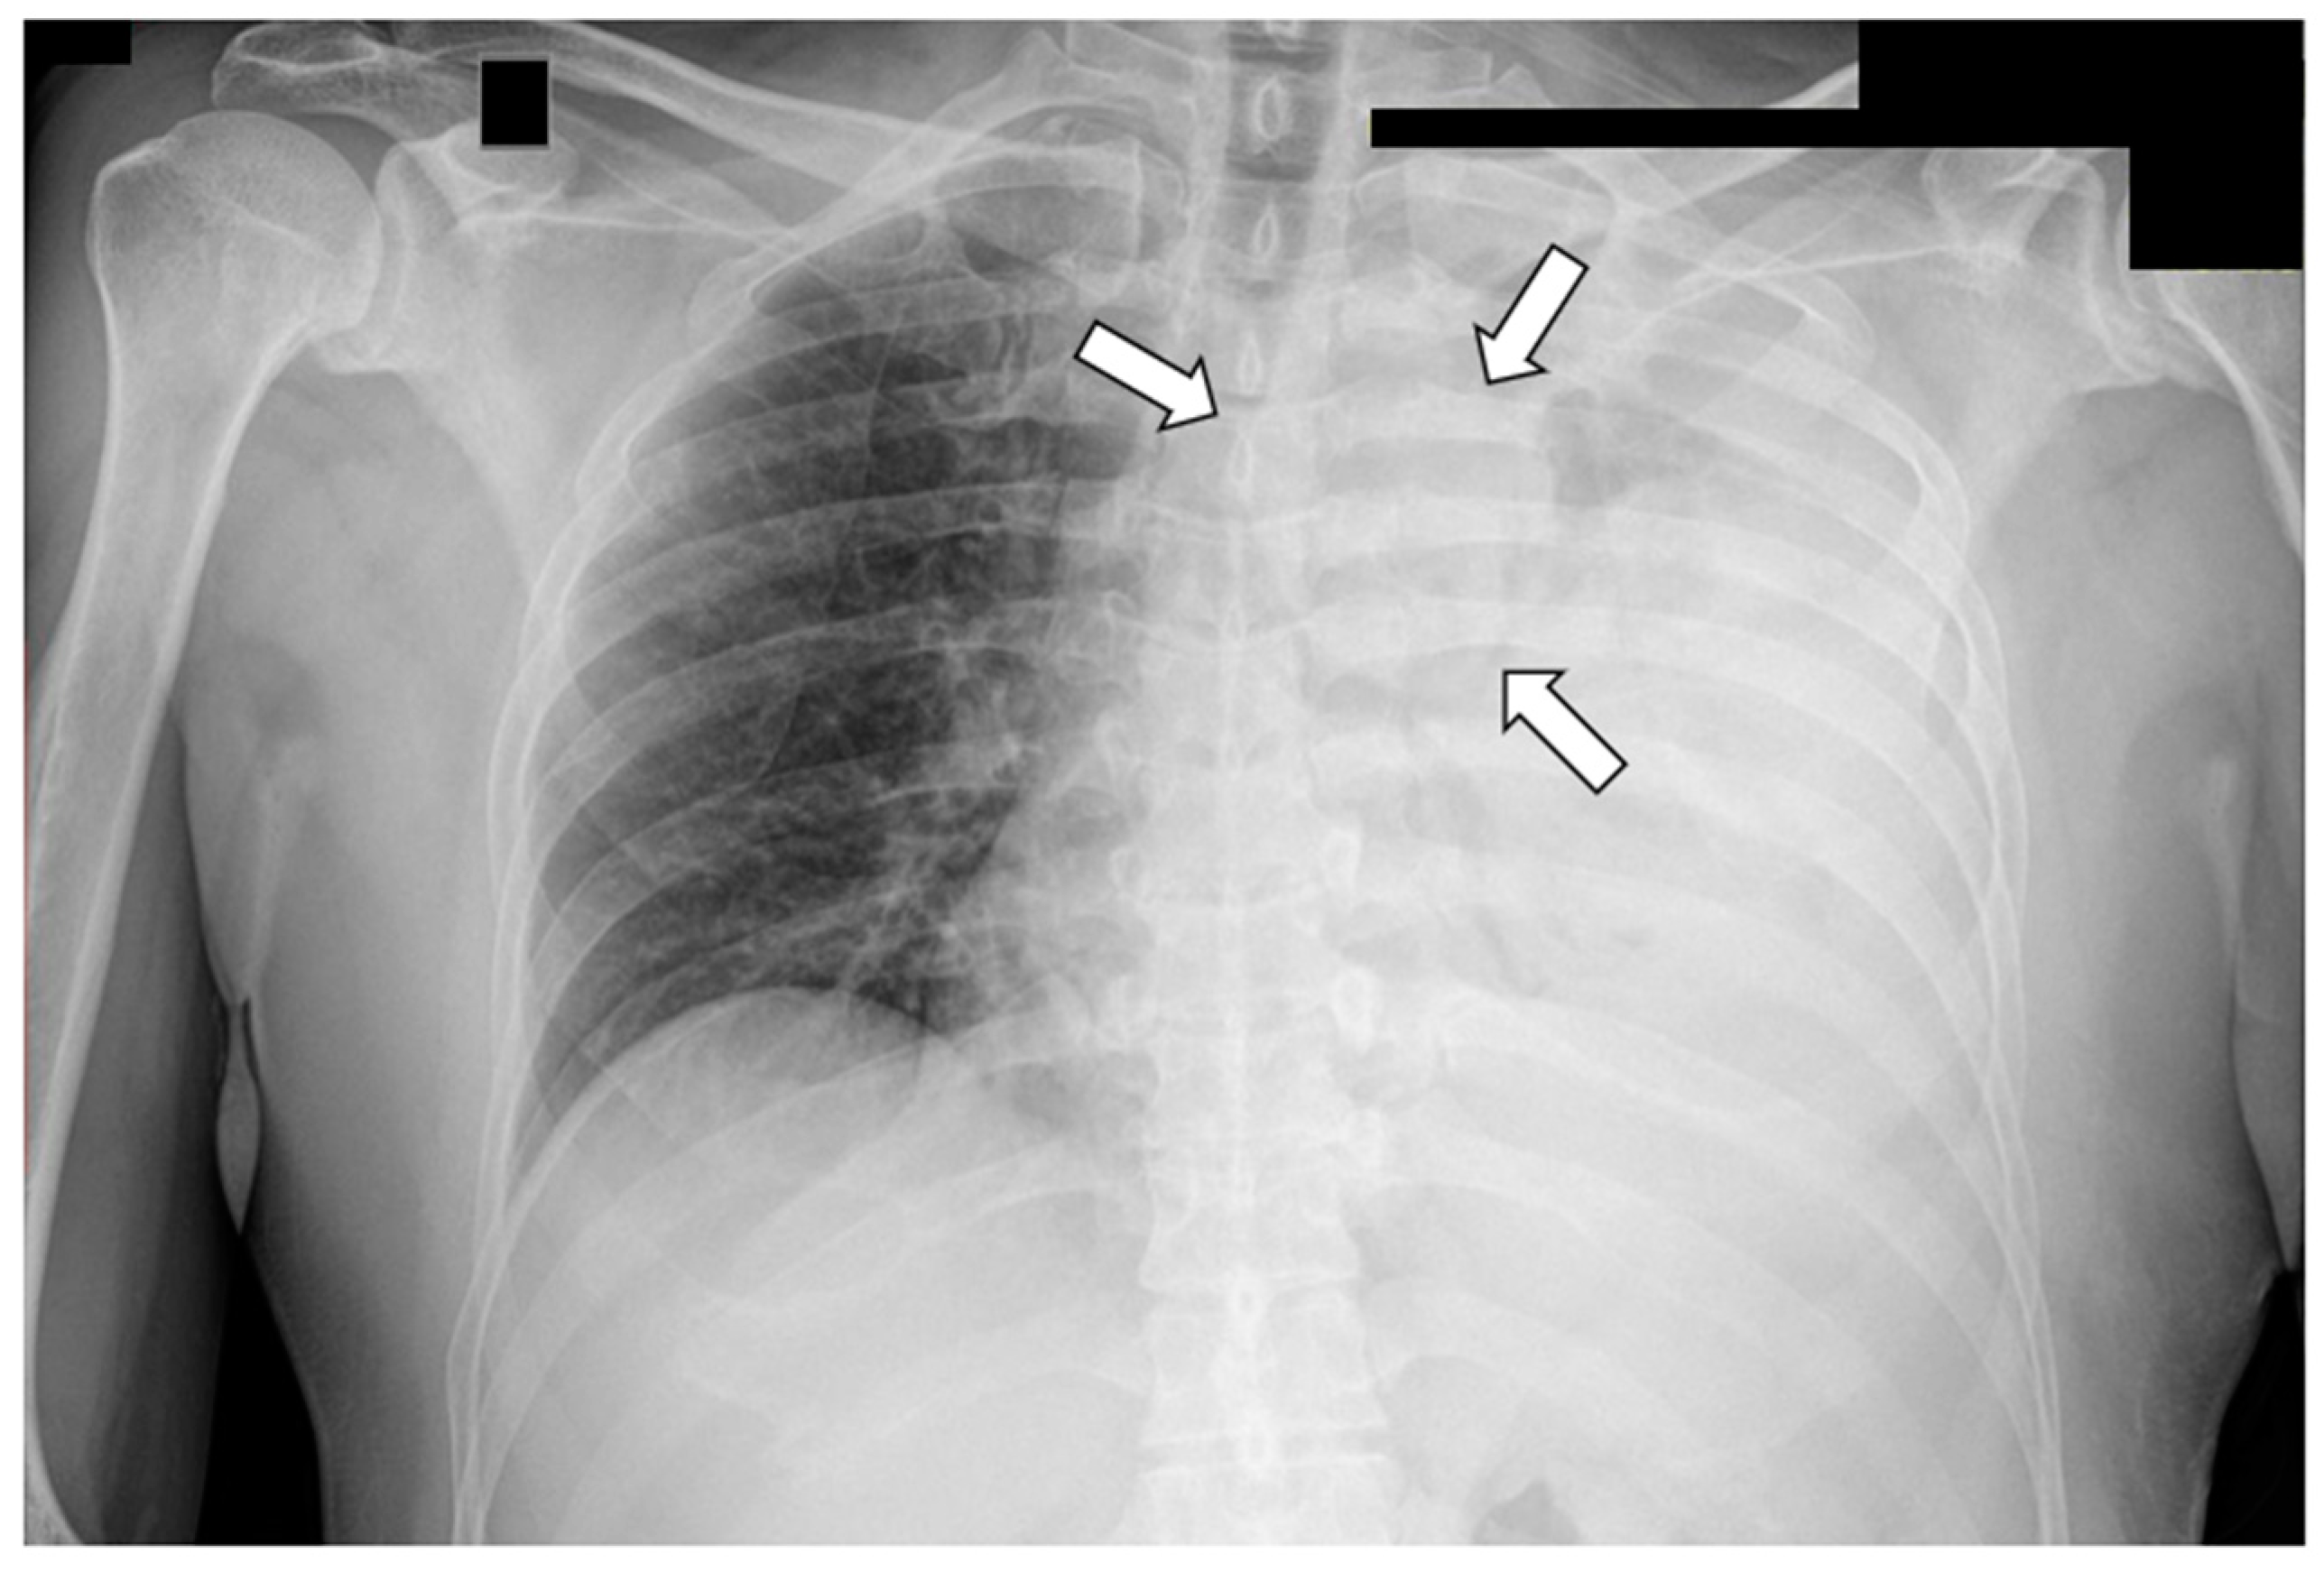

- Aroshidze, B.; Boyapati, L.; Pokhrel, A.; Gotlieb, V.; Khan, A.; Erdinc, B.; Cheema, M.A. Yolk Sac Tumor in the Anterior Mediastinum Presenting as Acute Pericarditis. Am. J. Case Rep. 2022, 23, e932616. [Google Scholar] [CrossRef]

- Tanase, B.; Burlacu, A.; Mugescu, M.; Neicu, A.; Radoi, S.; Constantinoiu, S.; Horvat, T. Malignant Extramucosal Esophageal Tumor—Yolk Sac Tumor—Case Report. Chirurgia 2022, 117, 222–229. [Google Scholar] [CrossRef]